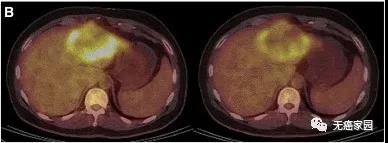

患者P9的PET/CT显示肿瘤活性明显减弱